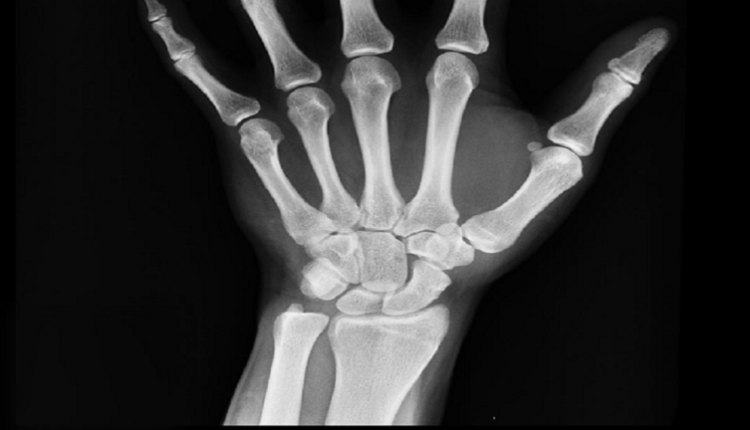

يتوفر في الاسواق أفضل مكمّلات غذائية للعظام والتي قد ترغب في إضافتها إلى نظامك الغذائي للحد من هشاشة العظام مع التقدم في العمر.

وتوصي الجمعية الملكية لهشاشة العظام بتناول الكالسيوم لاعتباره أفضل مكمّلات غذائية للعظام.

وأكدت أن “جسمك يحتوي على كيلوغرام واحد من الكالسيوم” – ويمكن العثور على 99% منه في العظام.